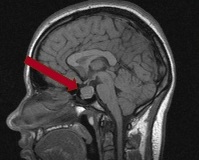

- МРТ головного мозга. Более информативна, чем рентгенография. Позволяет визуализировать интраселлярную опухоль гипофиза, определить ее размеры, инвазивность роста. Для аденомы характерно изменение размеров, структуры и формы турецкого седла.